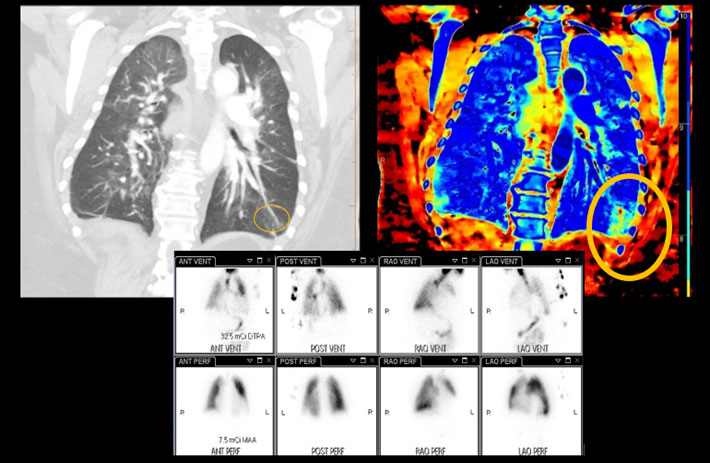

Mit dem Spektral-Detektor-CT werden Spektraldaten automatisch bei jedem Scan erfasst. Die Informationen stehen jederzeit auf der Scankonsole, der CT-Workstation sowie an jedem PACS-Arbeitsplatz zur Verfügung, sodass es nicht notwendig ist, den Patienten erneut zu scannen, bspw. wenn initial zufällige Anomalien festgestellt wurden. Dadurch profitieren Anwender durch eine höhere Diagnosesicherheit und weniger Nachuntersuchungen auf anderen bildgebenden Systemen. Unsere Fallsammlung zeigt, welchen klinischen Mehrwert der Spektral-Detektor-CT in unterschiedlichsten Anwendungsbereichen in der klinischen Routine bringt. Jede Woche gehen neue Fälle live.